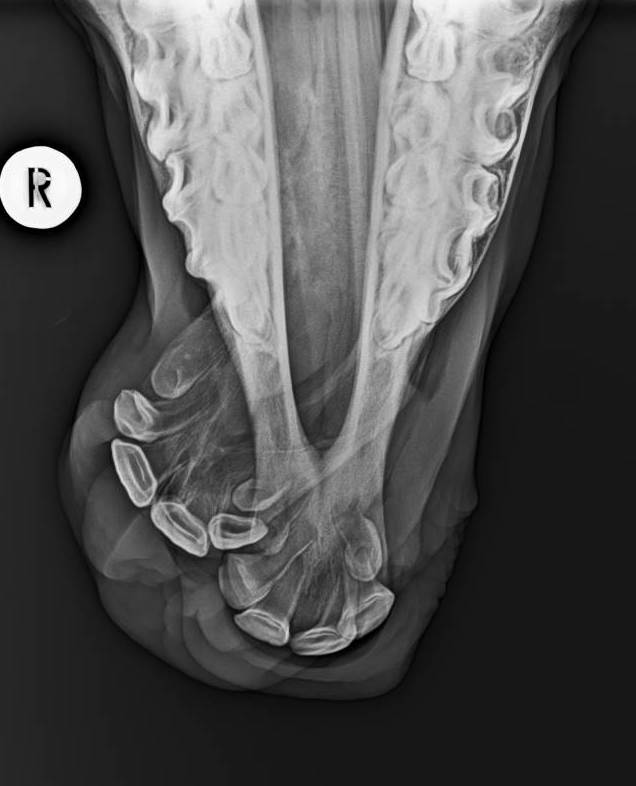

Baby Beanie and her wry nose

She suffers from a congenital deformity named Wry Nose, which as the names suggests is a twisted nose. This means her teeth did not occlude and she had great difficulty suckling, her nasal passages were partially obstructed and she had difficult breathing. Reconstructive surgery was the only option for Beanie and thanks to the entire team at Camden Equine Centre along with our specialist equipment we are happy to say Beanie’s is able to breath and eat properly and will go onto to live a happy life. We are very grateful to Beanies owners who trusted us with her care. for more info on Beanies case check ou

INFO: wry nose or “campylorhinus lateralis” is a congenital disease that is rare in horses. Foals are born with a deviated nasal passage an pre-maxilla. The causes of this deformity is not totally known. In most cases this creates a blockage of both nasal passages and foals will quickly die considering they are not able to breath. Rapid intervention to free the airway may be needed. In other cases where there is sufficient airflow foals can be nursed until they are old enough to undergo surgery. Depending on the degree of deformity the prognosis for athletic outcome without intervention is regarded as poor. Following surgery, if the airway can be reestablished properly the prognosis is good. It is a demanding intervention requiring a dedicated specialist staff and great financial commitment from owners, but it can be done.